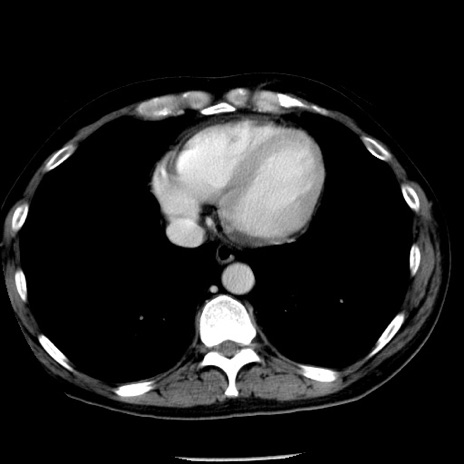

症例29(横断像)

【症例】40歳代男性

【現病歴】2日前から胃痛あり。徐々に周期的な激痛に変化した。本日になっても激痛があるため受診。

【身体所見】意識清明、BT 38-39℃台あり、腹部:膨満、やや硬、右下腹部に圧痛あり。

【データ】WBC 8500、CRP 23.26